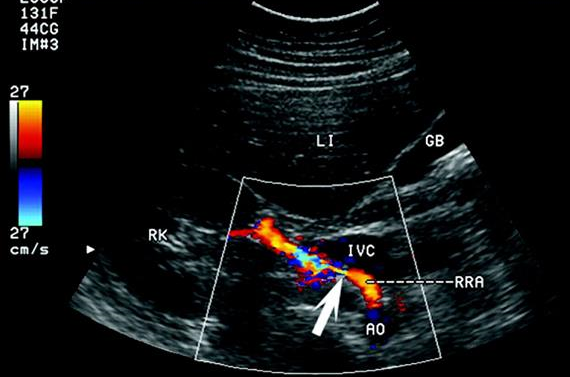

Цветная визуализация в комбинации с количественной оценкой кровотока стала стандартной диагностической процедурой при исследовании почти всего человеческого тела. Метод занял прочные позиции в таких дисциплинах как кардиология, сосудистая хирургия, акушерство и гинекология, неврология, трансплантология и др.

Не меньшее значение качественная и количественная оценка кровообращения (цветная Визуализация с анализом Допплеровского спектра) имеет при исследовании МОЧЕПОЛОВОЙ СИСТЕМЫ.

У нас накоплен большой многолетний опыт допплерографических исследований в области урологии, гинекологии и исследовании магистральных сосудов.